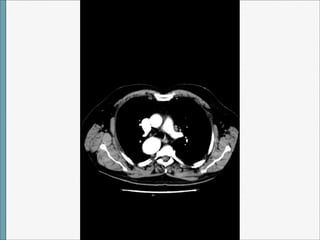

TAC

Arco Aórtico Derecho

1)CON ARTERIA SUBCLAVIA IZQUIERDA ABERRANTE

Volviendo al caso…

Tras acudir varias veces a urgencias por dolor torácico atípico (con constantes,

exploración,ECG, Bioquimica, hemograma y coagulación (incluido enzimas cardiacas)

completamente normales , se pidió interconsulta con Cardiología que citó en 2014 para

completar estudio con ecocardiograma y prueba de esfuerzo:Normales